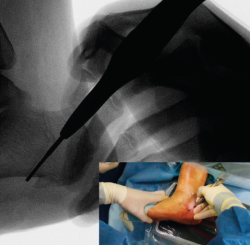

Figura 5. Imagen fluoroscópica del trazo dorsal de la osteotomía y su correspondencia en cirugía.

La fresa se coloca en línea con el trazo de osteotomía dibujado en la piel, primero el dorsal y después el plantar (Figuras 5 y 6), y va cortando la pared lateral y el hueso esponjoso del calcáneo y progresando paulatinamente hasta alcanzar la segunda cortical y cortarla cuidadosamente. Se recomienda no superar en 6.000 rpm la velocidad de la fresa para evitar la osteonecrosis térmica. A pesar de que el procedimiento se realiza sin isquemia para que la sangre refrigere el calor de la fresa, se recomienda que el ayudante aporte suero salino para contribuir a tal efecto.